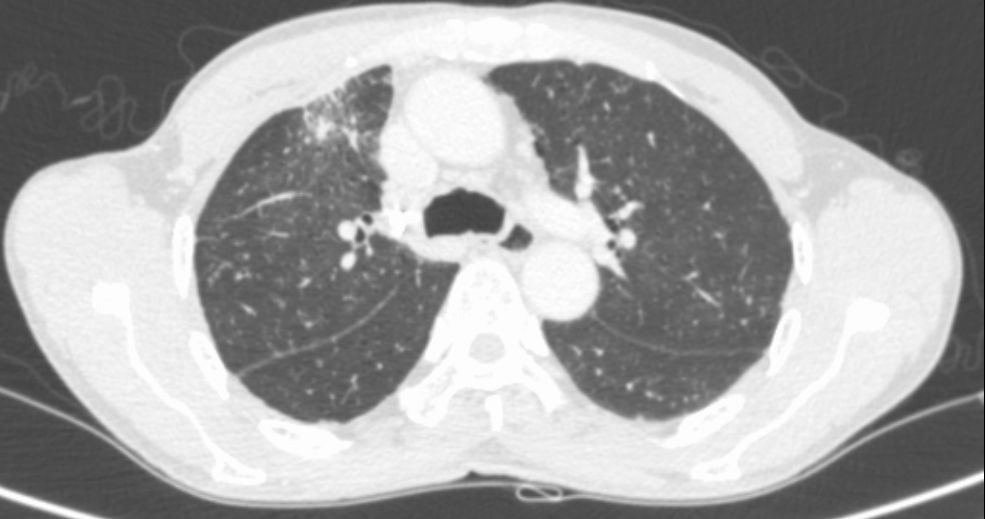

经与患者及家属充分沟通后,呼吸与危重症医学科三区为吴伯安排了肺结节微波消融术。术前已行结节活检,病理结果提示为腺癌。手术过程中,在副院长许承琼指导下,通过CT引导定位,布针顺利平稳,布针结束后,随即展开肺结节微波消融术,手术历时不到2小时顺利结束。

肺结节消融术,尤其是微波消融,是一种局部热消融技术,以创伤小、安全性高和可重复性强为特点,射频消融通过生物学效应,使肿瘤细胞发生不可逆损伤或凝固性坏死,形象地说,就是将肿瘤“烧死”,达到“灰飞烟灭”的效果。